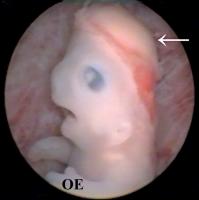

Embryo - Gesicht - Obere Extremität

Abbildung 2a-b: Detailansicht des Gesichts (Abb. 2a) und der oberen Extremität (OE) (Abb. 2b) eines Embryos in der 7. Entwicklungswoche. Die Augenlider beginnen sich über den pigmentierten Augen auszubilden. Finger sind deutlich erkennbar, aber noch flossenartig. Bestimmte Handmalformationen, wie z. B. eine Syndaktylie, können erst nach der 7. Entwicklungswoche diagnostiziert werden.